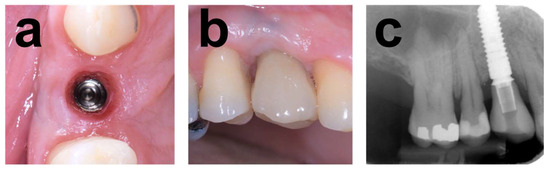

2.7.1. Case 1